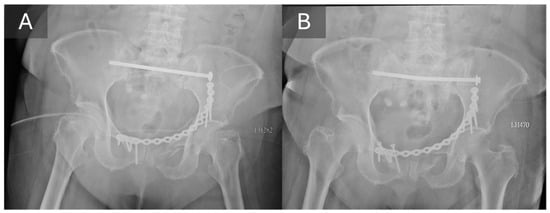

3.3. Radiographic Outcomes